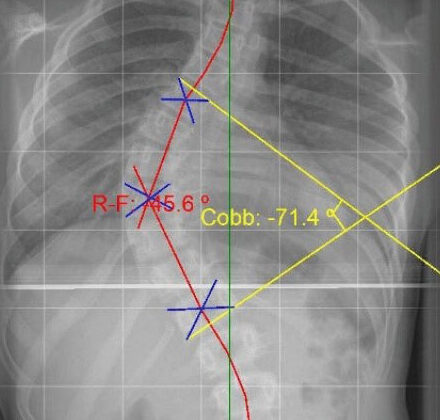

يتم قياس اعوجاج العمود الفقري باستخدام زاوية كوب، وهي المعيار الأساسي للحكم على الخطورة:

أقل من 20 درجة: غالبًا خارج مرحلة الخطر، وتحتاج متابعة فقط

من 20 إلى 40 درجة: مرحلة تحذيرية، خاصة أثناء النمو

أكثر من 40–45 درجة: غالبًا تُعد مرحلة خطر حقيقي

عند هذه الدرجات، يزيد احتمال التفاقم، ويقل تأثير العلاج البسيط إذا لم يتم الالتزام به بدقة.